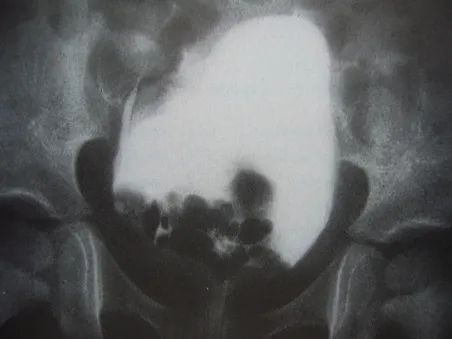

A hormone-secreting tumour that can occur in the adrenal glands. Phaeochromocytomas usually develop in the small glands on top of the kidneys (adrenal glands). They most commonly affect people between the ages of 20 and 50, but can occur at any age. Because of hormones secreted, symptoms include high blood pressure, sweating, rapid heartbeat and headache. Surgery to remove the tumour is usually required.